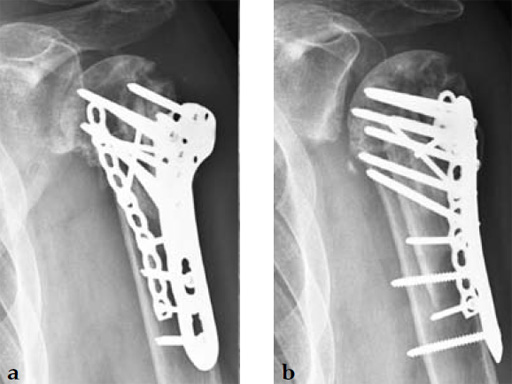

3.5 mm LCP Periarticular Proximal Humerus

A 72-year-old woman suffered a four-part fracture of the left proximal humerus following a fall from a standing height. The patient underwent open reduction and internal fixation of the proximal humeral fracture.

Case provided by Dean G Lorich, New York, New York, USA